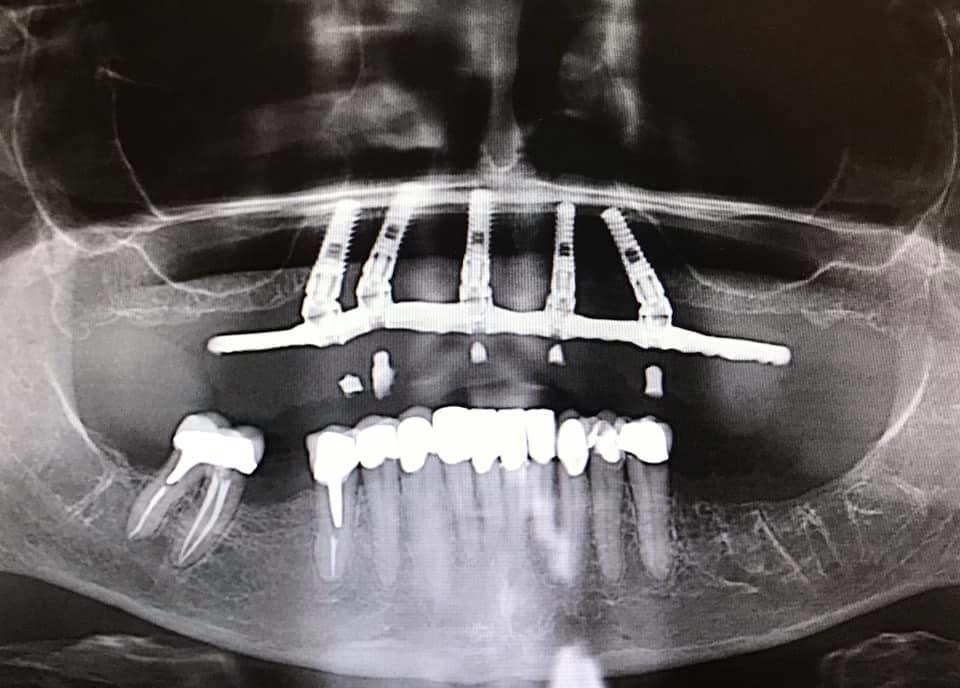

implant supported lower denture

For a cost-effective way of replacing many missing teeth, dentures can be held securely in place with implants, providing a great improvement from traditional removable dentures.

All- On- 5 technique: Implant Retained Dentures that patient does not remove